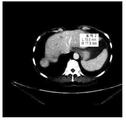

- 238000002591 computed tomography Methods 0.000 description 1